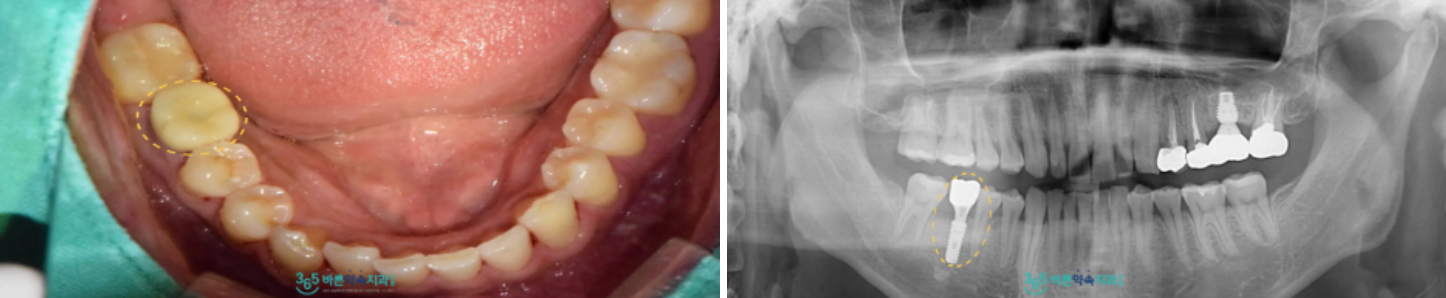

치아에 브라켓을 붙여

공간을 확보하기 위한

교정치료를 진행하였으며

정기적인 검진을 통해

치아의 이동 상태를 확인하였는데요.

검진 때마다 눈에 띄게

아래턱 오른쪽 두 번째 큰 어금니(#47)가

자기 위치로 이동하는 것을

확인할 수 있었습니다.